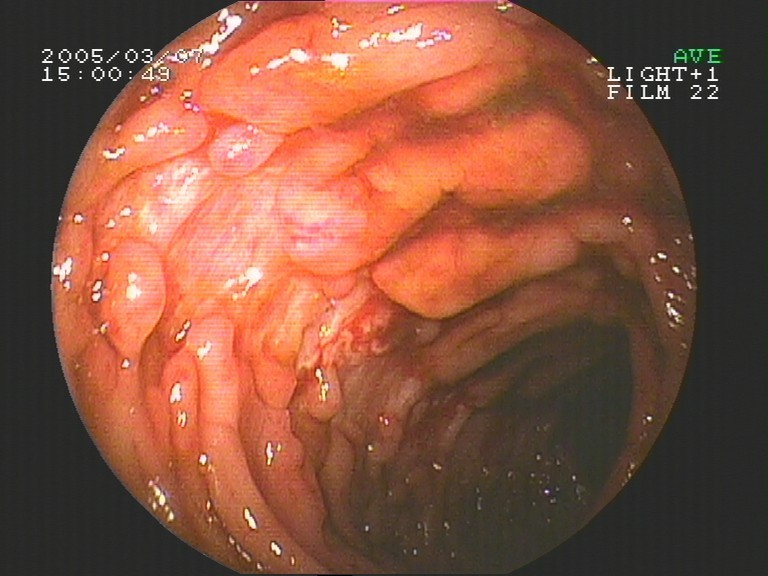

Coloskopie - Ileum terminale (unterster Dünndarmabschnitt)